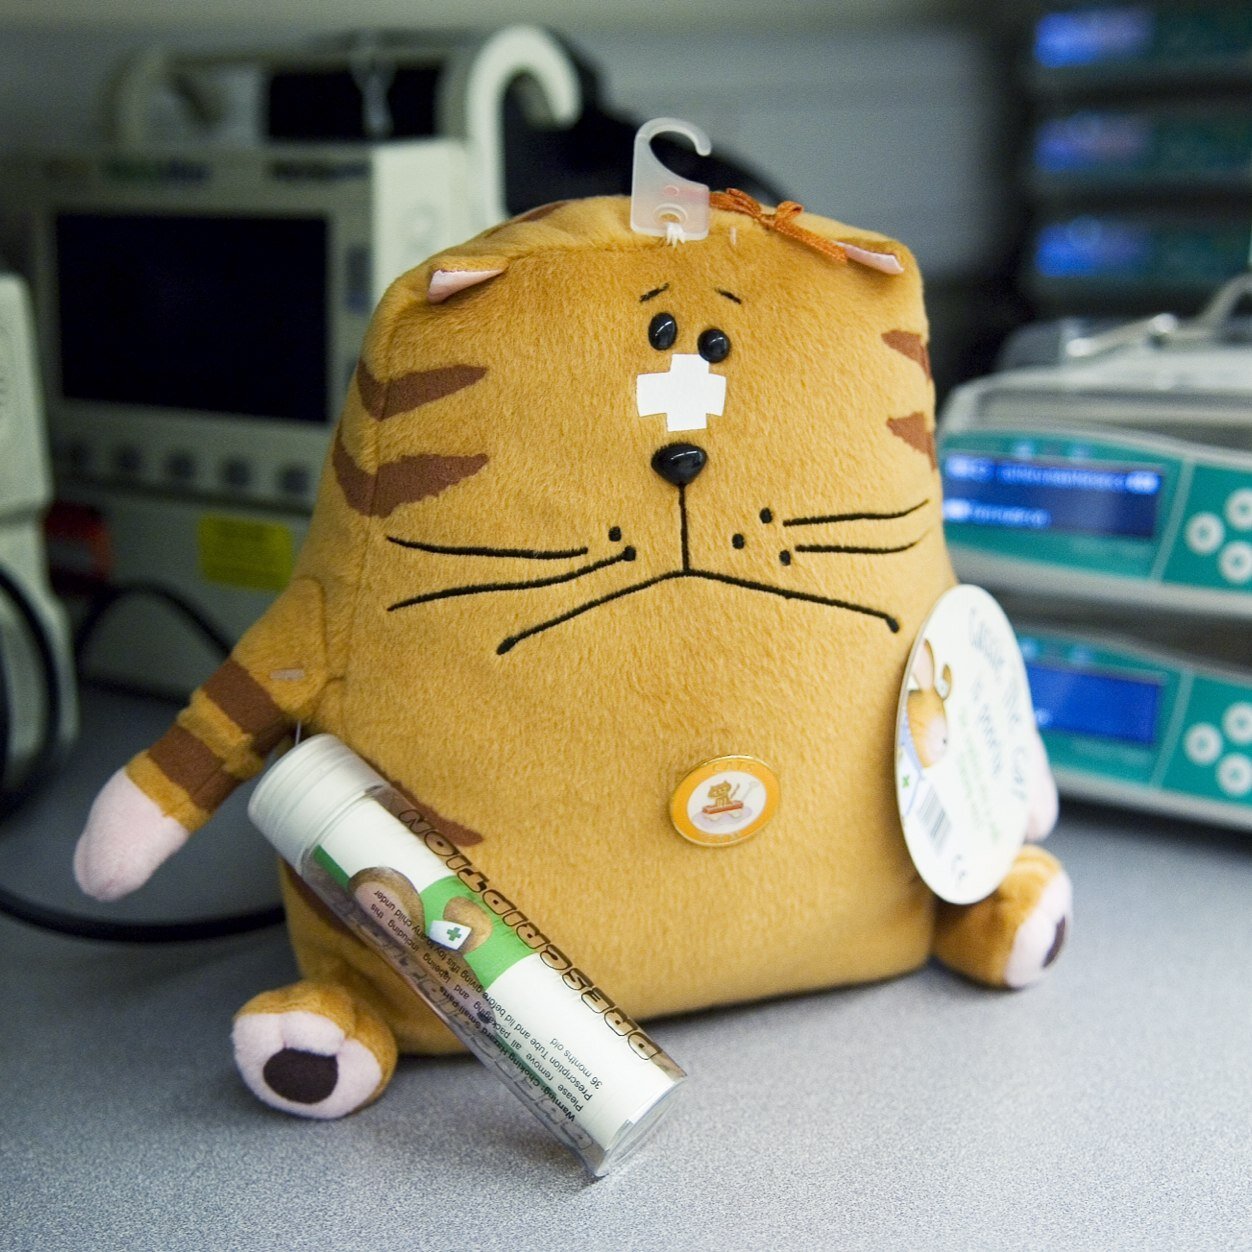

Emergency transport service for babies & children. Advice, care & coordination, medical transport & critical care retrieval by road, helicopter &/or plane

Twin boys reunited with police, health care workers after emergency birth in north-west NSW - ABC News Well done to everyone involved in saving these precious babies. NETS is proud to played a part in this great story! @nswpolice @NSWHealth abc.net.au/news/2023-02-2…